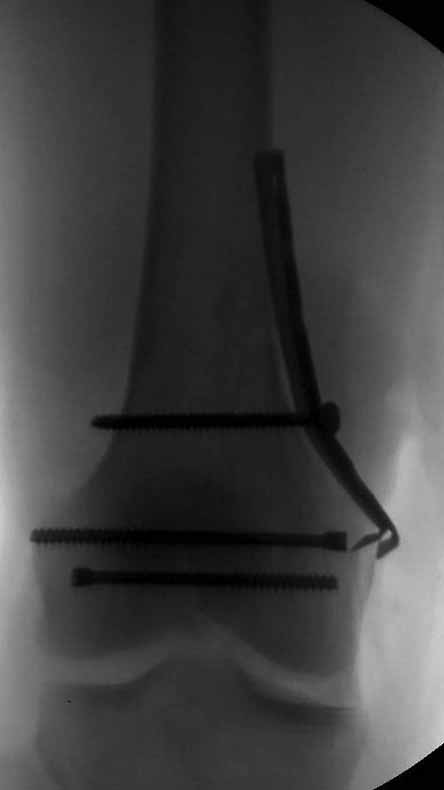

Коллеги, извиняюсь за задержку с результатом. Через медиальную артротомию обнажили н/3 бедра, отрепонировали внутренний мыщелок, затем по нему сопоставили суставную поверхность бедра с латеральным мыщелком.

Больная выписана в ортезе с регулируемым углом сгибания в колене, с рекомендациями через 3 нед. удалить спицы и начать разрабатывать сустав.

По прямому снимку репозиция удалось, поздравляю! А с латеральной стороны подозрение на флексионный компонент латерального мыщелка остается, а снимок получился косым, надо было бы повторить.

Выбор имплантов не совсем удачный, подкожно выступающие болты в мыщелках вскоре могут привести к проблемам. Вместо солитарной фиксации болтом-стяжкой дистально можно было бы добавить пару винтов, которые создали бы ротационную стабильность и межфрагментарную компрессию.

Возможно, есть скрытый замысел, неочевидный для нас - не понятны латерально оставленные спицы. Спицы возможный очаг вторичного осложнения, и, тем более у взрослых, тонкие спицы не создают адекватную фиксацию.

Djoldas,скрытого смысла в спицах нет. Без них латеральный мыщелок получается фиксированным только к медиальному, который, в свою очередь, фиксирован к проксимальному отломку. Соответственно латеральный мыщелок не фиксирован к бедру. Спицами мы попытались создать какую-никакую-стабильность латерального мыщелка относительно проксимального отломка бедра.

Болт-стяжка, на мой взгляд, создает не меньшую межфрагментарную компрессию чем винты. Не понял относительно ротационной стабильности винтов.